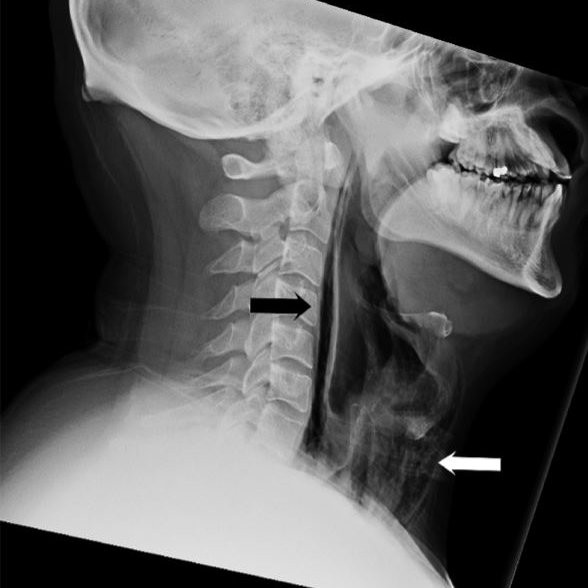

Sau khi xem xét và khám tổng thể, các bác sĩ nghe thấy âm thanh lạ rít lên và kéo dài từ cổ đến xương sườn, đây là một dấu hiệu cho thấy bong bóng khí đã đi vào các mô sâu và cơ bắp trong ngực. Sau khi chụp CT thì bác sĩ đã chắc chắn kết luận rằng, do anh nhịn hắt hơi quá lâu khiến luồng hơi đi ngược lại và tạo ra một lỗ thủng phía sau cổ họng.